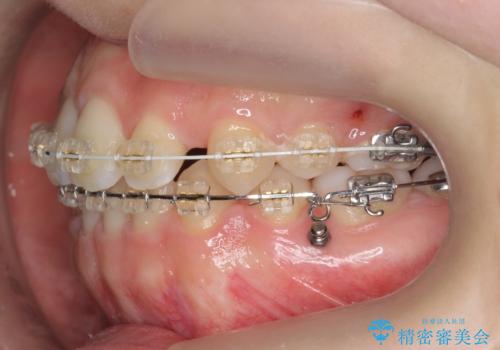

かみ合わせが悪いところを ワイヤー矯正でしっかり治療 マウスピース矯正は難しい症例

- ワイヤー矯正

前歯、奥歯ともに反対咬合になっており、また上顎の前歯が少し突出気味でした。

上下左右の小臼歯を抜歯しています。

臼歯の反対咬合は簡便なマウスピース矯正で治すのは難しいです。